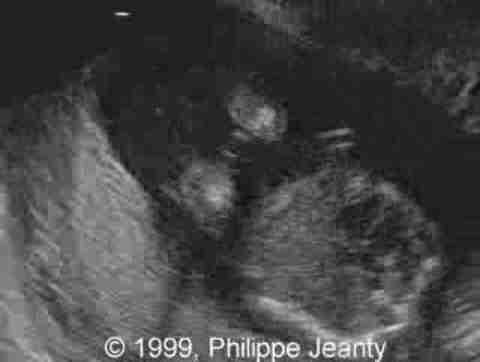

17-year-old primigravida.

This examination is obtained at 18 weeks amenorrhea.

• abnormal fingers,

• micrognathia,

• large eyes and possibly buphophtalmos

Very few, however, made the most crucial observation: the great disproportion between the head and abdomen. That disproportion is very typical of triploidy (see the lecture on aneuploidy for another example) and I know of no other conditions where such a big difference exist without a concomitant intracranial anomaly such as hydrocephaly, or teratomas… Of course, one of you will come up with a great differential diagnosis and then we will learn even more !